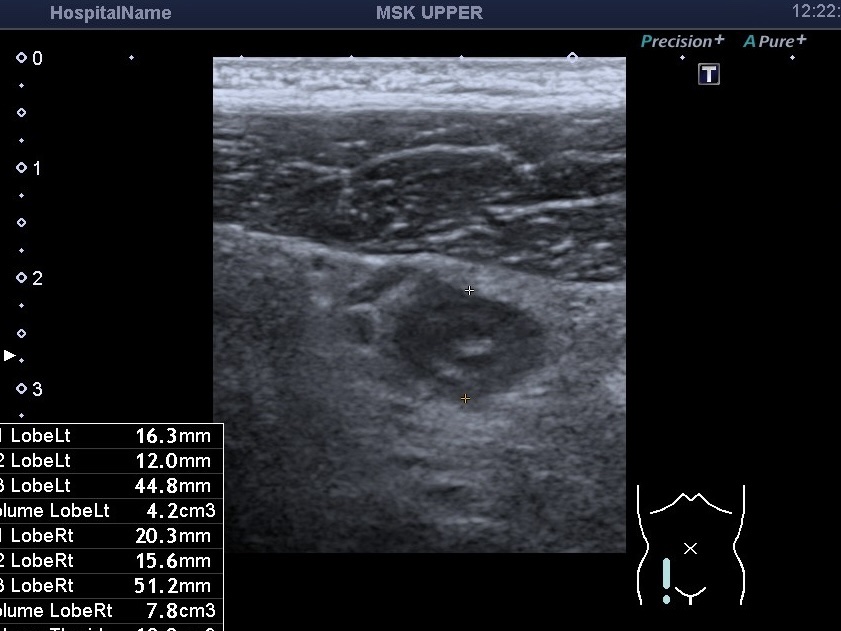

На знімках представлений випадок гострого апендициту у молодого чоловіка. Біль при цьому був не сильний, за словами пацієнта, він ходив із ним протягом 5 днів. При цьому пацієнт звертався до гастроентеролога в приватну клініку, і під час обстеження лікар не виявив ознак гострого апендициту. Проте лікар призначив УЗД органів черевної порожнини.

Під час УЗД було виявлено збільшений апендикс із ще збереженою пошаровою структурою, який не стискався при компресії датчиком і був болісним при натисканні. Навколо відзначалася змінена жирова клітковина та збільшені мезентеріальні лімфатичні вузли. Пацієнта того ж дня було направлено до хірурга та прооперовано. Хірург підтвердив, що вже мав місце флегмонозний апендицит.